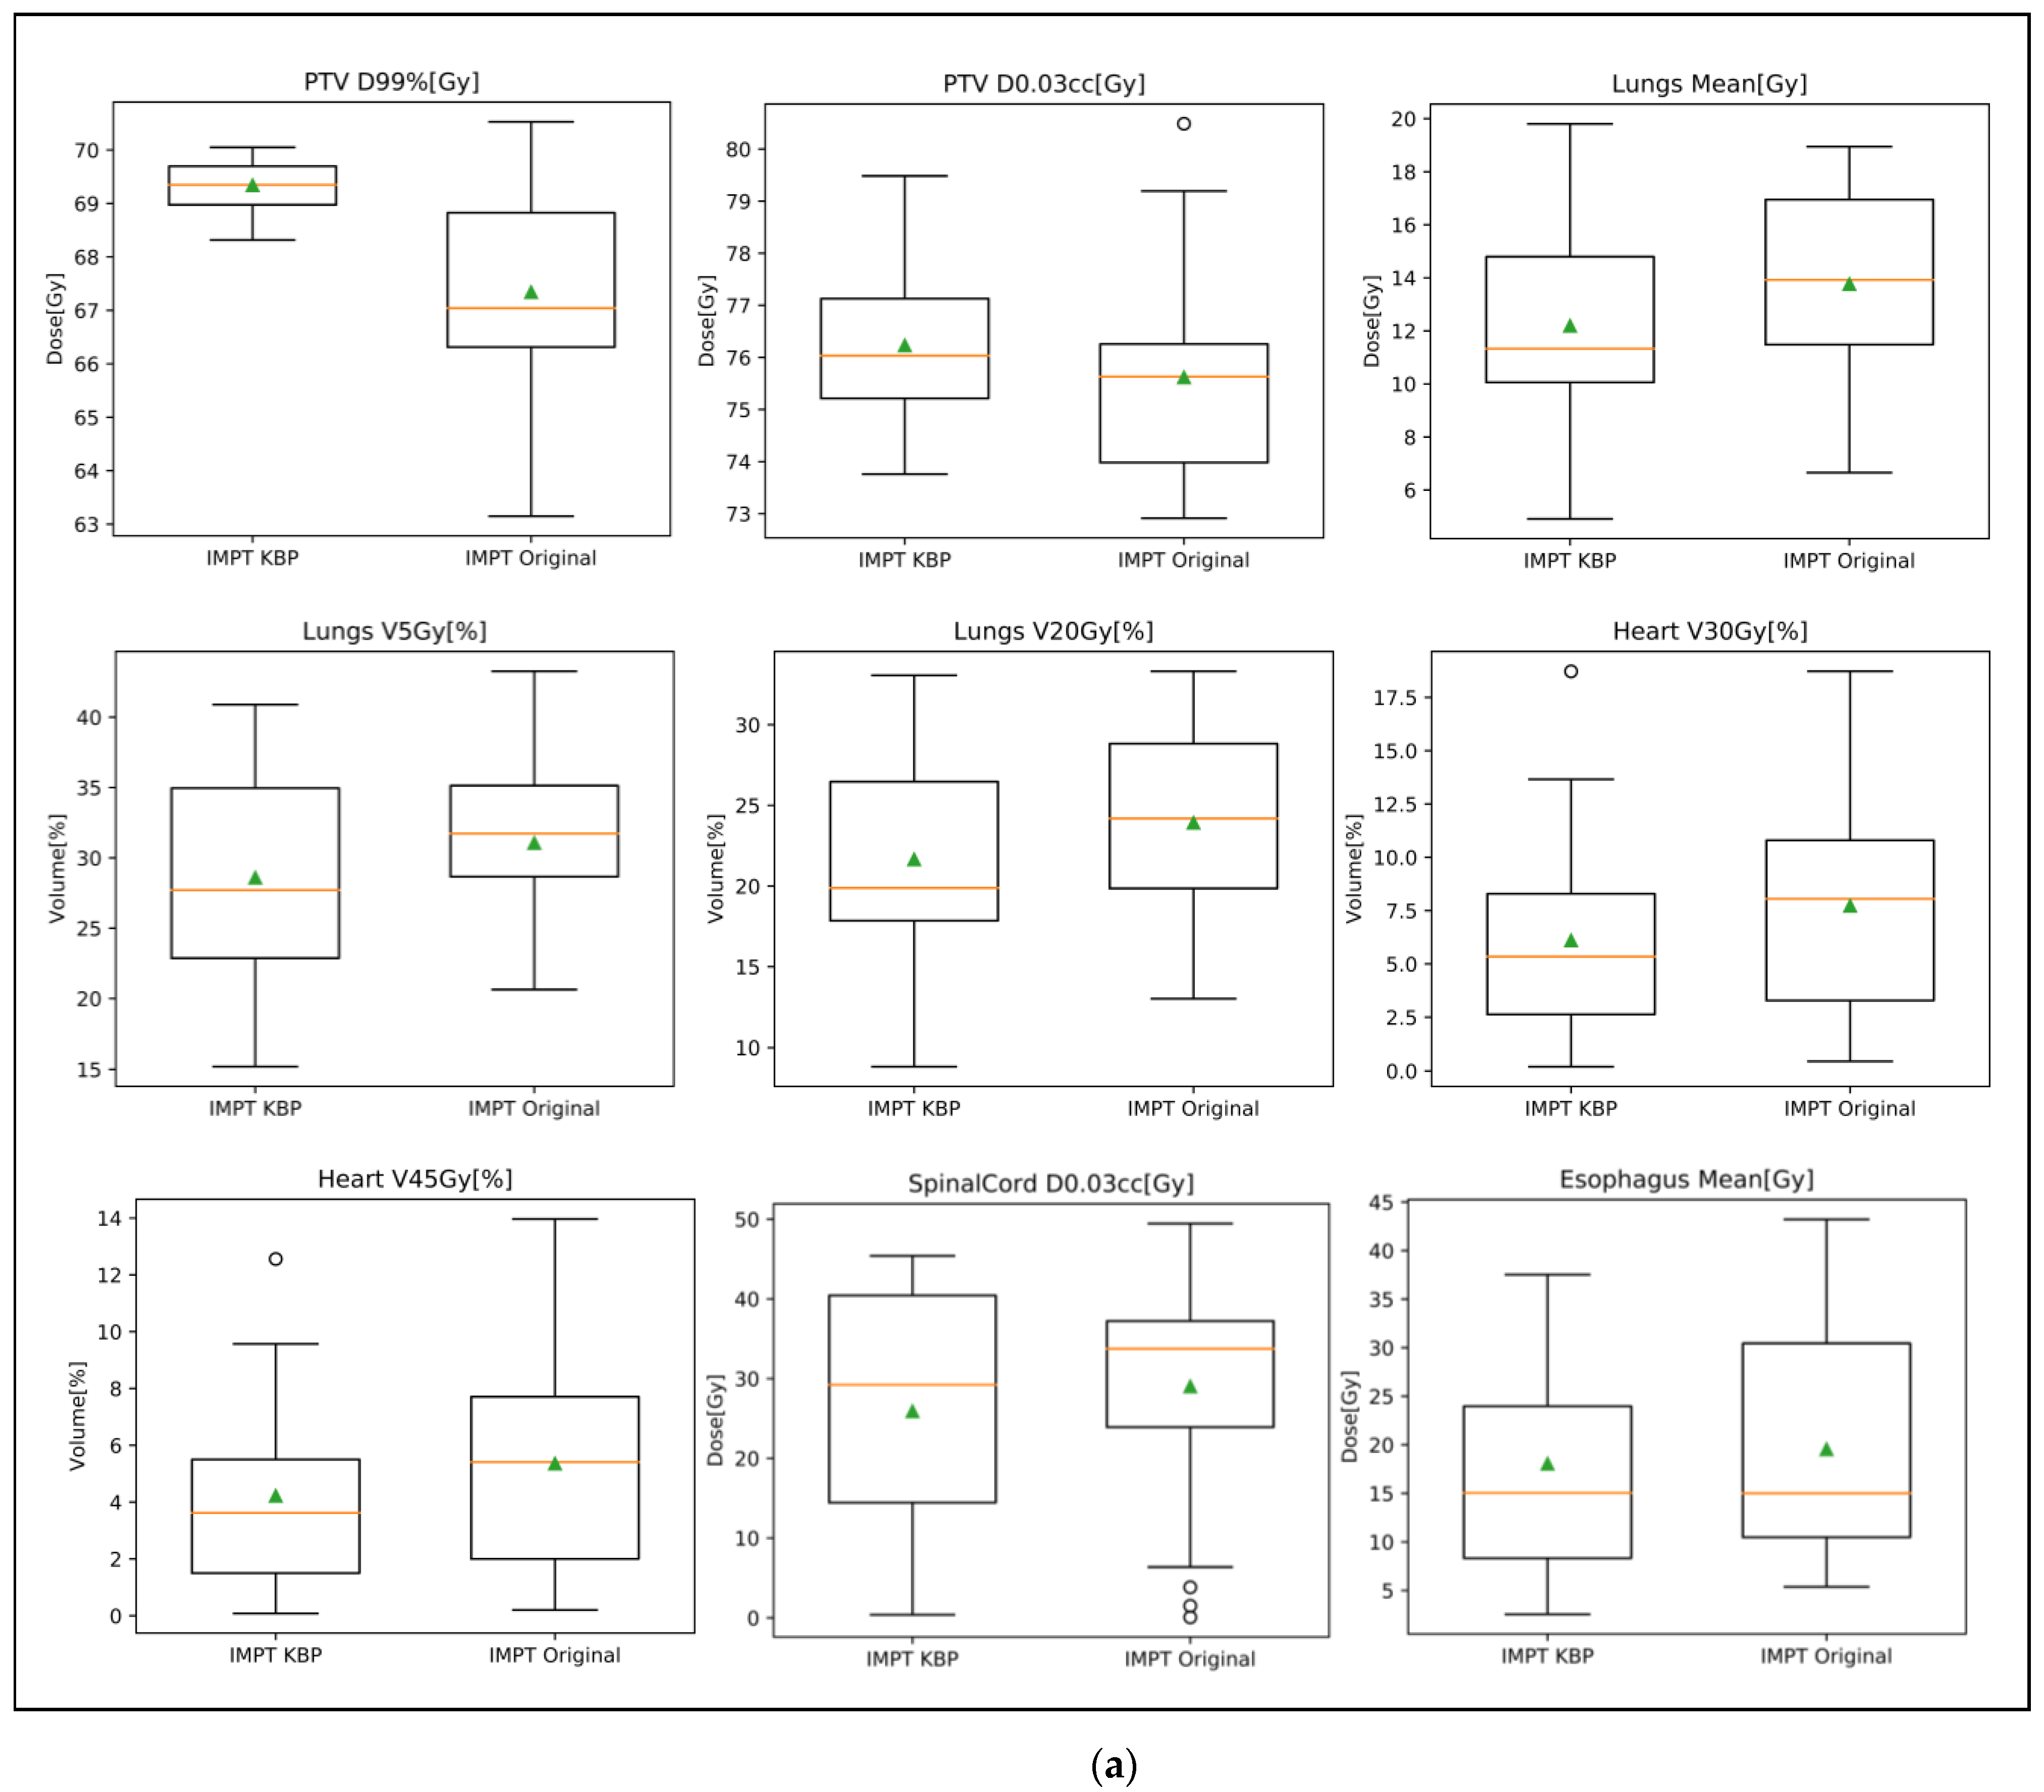

3.3. Plan Quality Review

| Structure Name | Dose Point | Manual | KBP | p Value |

|---|---|---|---|---|

| PTV | D95%[Gy] | 69.43 ± 0.52 | 70.20 ± 0.29 | <0.0001 |

| D0.03cc[Gy] | 79.65 ± 1.37 | 79.73 ± 1.63 | 0.4345 | |

| D99%[Gy] | 67.74 ± 0.93 | 68.89 ± 0.74 | <0.0001 | |

| Heart | V45Gy[%] | 6.2 ± 6.1% | 4.9 ± 5.0% | <0.0001 |

| V30Gy[%] | 8.6 ± 7.5% | 7.0 ± 6.4% | <0.0001 | |

| Mean[Gy] | 6.35 ± 5.07 | 5.26 ± 4.34 | <0.0001 | |

| Lungs | V5Gy[%] | 31.8 ± 8.7% | 31.0 ± 8.9% | 0.0022 |

| V20Gy[%] | 23.0 ± 6.1% | 22.5 ± 6.4% | 0.0039 | |

| Mean[Gy] | 13.11 ± 3.38 | 12.81 ± 3.64 | 0.0028 | |

| Esophagus | V74Gy[cc] | 0 ± 0 | 0 ± 0 | N/A |

| Spinal Cord | D0.03cc[Gy] | 41.06 ± 9.80 | 40.58 ± 10.63 | 0.3579 |

| Structure | Dose Point | IMPT Original | IMPT KBP | p Value | PS Original | IMPT KBP | p Value |

|---|---|---|---|---|---|---|---|

| PTV | D95%[Gy] | 69.60 ± 1.26 | 70.37 ± 0.16 | 0.0127 | 69.44 ± 3.39 | 70.30 ± 0.44 | 0.2497 |

| D0.03cc[Gy] | 75.62 ± 2.09 | 76.23 ± 1.54 | 0.2999 | 79.249 ± 3.97 | 76.11 ± 1.29 | 0.0053 | |

| D99%[Gy] | 67.34 ± 2.10 | 69.34 ± 0.48 | 0.0006 | 65.50 ± 5.08 | 69.14 ± 0.73 | 0.0044 | |

| Heart | V45Gy[%] | 5.4% ± 3.9% | 4.2% ± 3.3% | 0.0043 | 5.6% ± 5.5% | 4.2% ± 4.4% | 0.0001 |

| V30Gy[%] | 7.7% ± 5.2% | 6.1% ± 4.6% | 0.0048 | 7.6% ± 6.7% | 5.9% ± 5.6% | 0.0003 | |

| Mean[Gy] | 6.25 ± 4.07 | 4.92 ± 3.54 | 0.0032 | 5.46 ± 4.74 | 4.60 ± 4.12 | 0.0208 | |

| Lungs | V5Gy[%] | 31.1% ± 6.2% | 28.6% ± 7.6% | 0.0111 | 33.4% ± 10.8% | 28.8% ± 9.4% | <0.0001 |

| V20Gy[%] | 23.9% ± 6.0% | 21.6% ± 6.6% | 0.0063 | 25.9% ± 7.9% | 22.04% ± 8.14% | <0.0001 | |

| Mean[Gy] | 13.76 ± 3.61 | 12.19 ± 3.98 | 0.002 | 14.64 ± 4.43 | 12.68 ± 4.43 | <0.0001 | |

| Esophagus | V74Gy[cc] | 0.05 ± 0.22 | 0.01 ± 0.04 | N/A | 0.80 ± 2.48 | 0.01 ± 0.03 | N/A |

| Spinal Cord | D0.03cc[Gy] | 29.02 ± 14.80 | 25.90 ± 15.52 | 0.2197 | 27.26 ± 16.55 | 33.20 ± 13.75 | 0.0466 |